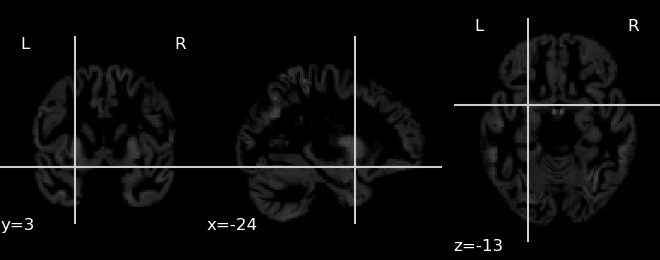

To understand which regions of the brain are important in the decision making process we perform a slightly modified version of occlusion analysis proposed in [30] to fit our data. In this analysis, usually a part of the scan is occluded with gray or white patch and the output from the network is recalculated. The occluded region is considered to be important if the probability of the target class decreases compared to the original image. The heatmap of relevance is calculated by sliding the patch across the image and plotting the difference in the probability. In our case we repeated the procedure twice, once for each of the GM and WM images. The resultant heatmaps are presented in Fig. 5, where the important areas are marked in red.

![]() |

| (a) Heatmap for White Matter |

| (b) Heatmap for Gray Matter |

To better understand the above heatmaps we also calculated the relevance per brain area using methods provided by [30] which is presented in Fig. 7 and Fig. 7. We can see for Gray Matter the most focused on area is Superior Frontal Gyrus and for White Matter it is Postcentral Gyrus.